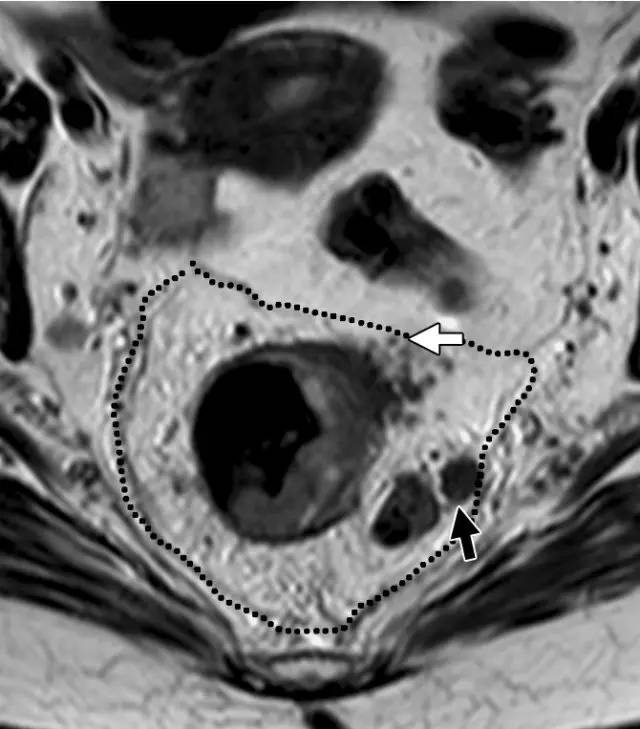

图 29 轴向 T2 加权图像报告 CRM 的距离。虚线描绘了直肠系膜筋膜,这是 T3a 肿瘤的 CRM,预测 CRM 阴性

图 30 轴向 T2 加权图像报告 CRM 的距离。T3a 肿瘤远离直肠系膜筋膜(黑色箭头),但直肠系膜筋膜上的可疑淋巴结(白色箭头)提高了 CRM 阳性(CRM = 0 mm)的可能性。

图 31 轴向 T2 加权图像报告 CRM 的距离。T3d 肿瘤局限于固有肌层内,肿瘤毗邻直肠系膜筋膜(箭头;肿瘤为 T2)。侵犯边界似乎是左后方(白色箭头),肿瘤的 CRM 评估为 5 mm。但有两个混合信号强度淋巴结(黑色箭头)邻接直肠,导致 CRM 为 0 mm。

图 32 轴向 T2 加权图像报告 CRM 的距离。T3c 肿瘤,靠近腹膜的 EMVI(白色箭头)和不规则信号强度淋巴结的 T3c 肿瘤,通过毗邻直肠系膜筋膜的淋巴结包膜(黑色箭头)肿瘤扩展(预测 CRM = 0 mm)。

口诀 6:「E」